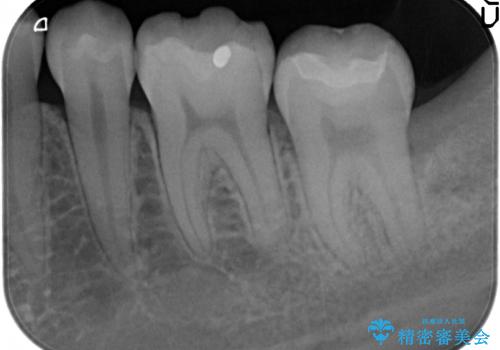

- 古い銀歯を白くしたいといらっしゃった方の症例です。

銀歯及び虫歯を除去後、セラミックインレーにて修復を行いました。